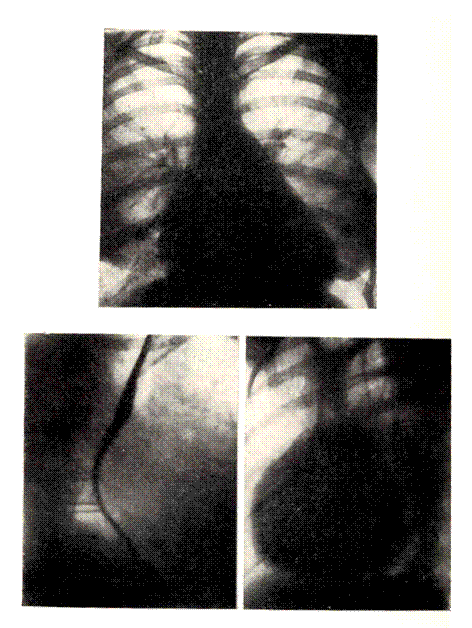

РЕНТГЕНОГРАММЫ БОЛЬНОГО С КОМБИНИРОВАННЫМ МИТРАЛЬНЫМ ПОРОКОМ.

На передней рентгенограмме значительное расширение сердца в поперечнике с выраженной митральной конфигурацией. Правый корень широкий и конически разветвлен. Справа в базально-латеральном отделе — линии Керли. В первом косом положении контрастированный пищевод оттеснен по дуге большого радиуса. Во втором косом положении увеличение обоих желудочков и левого предсердия.